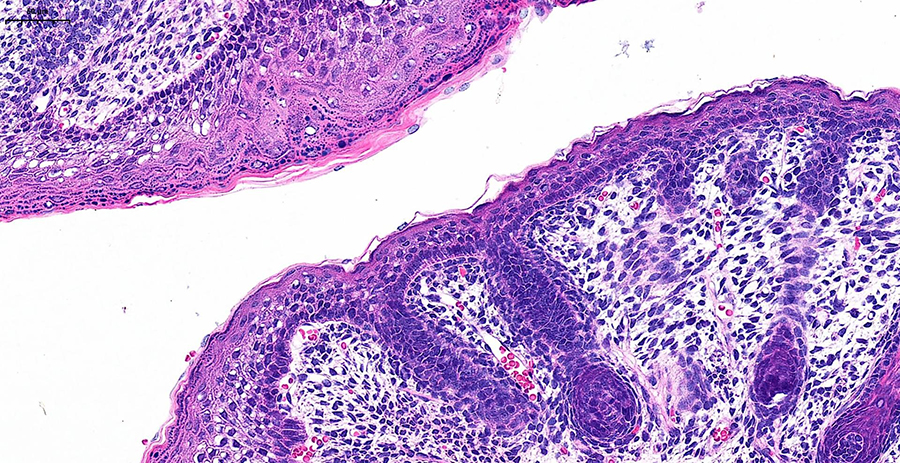

Сможете оценить высочайшее разрешение, скорость обработки (полное стекло за 3-5 минут) и интеллектуальное аналитическое ПО, которое автоматически распознаёт структуры и формирует количественные отчёты с готовыми данными. Можно принести для апробации свои образцы, демонстрируемая конфигурация флуоресцентных каналов (Ex/Em, нм):